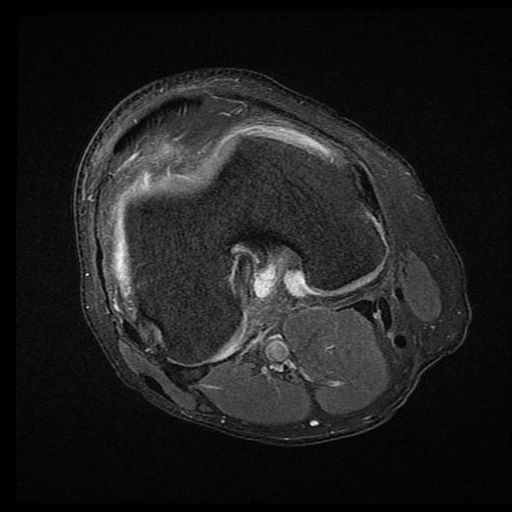

Hội chứng chèn ép túi mỡ trước đùi (Prefemoral fat pad impingement syndrome)